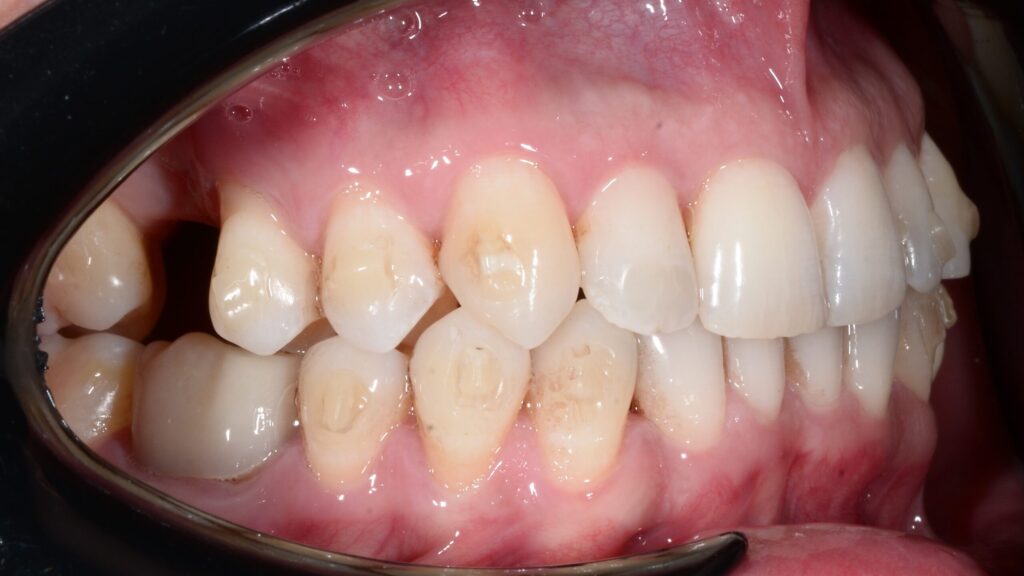

In this orthodontic case, Dr. Timpu-Dascalu addressed an anterior crossbite, a misalignment that can lead to functional issues and aesthetic concerns.

To correct the anterior cross-bite, the doctor utilized a comprehensive approach focusing on biomechanics to ensure precise tooth movement. This approach allowed her to achieve a stable and functional occlusion, improving both the patient’s bite and smile.

The treatment focused on correcting the anterior crossbite while simultaneously addressing both transversal and sagittal discrepancies. The primary goals were to expand both the upper and lower arches, derotate the molars, and address the uncontrolled tipping of tooth 12. Spark 20 package was selected to achieve the orthodontic goals. The treatment plan was meticulously developed using Spark’s Approver software.